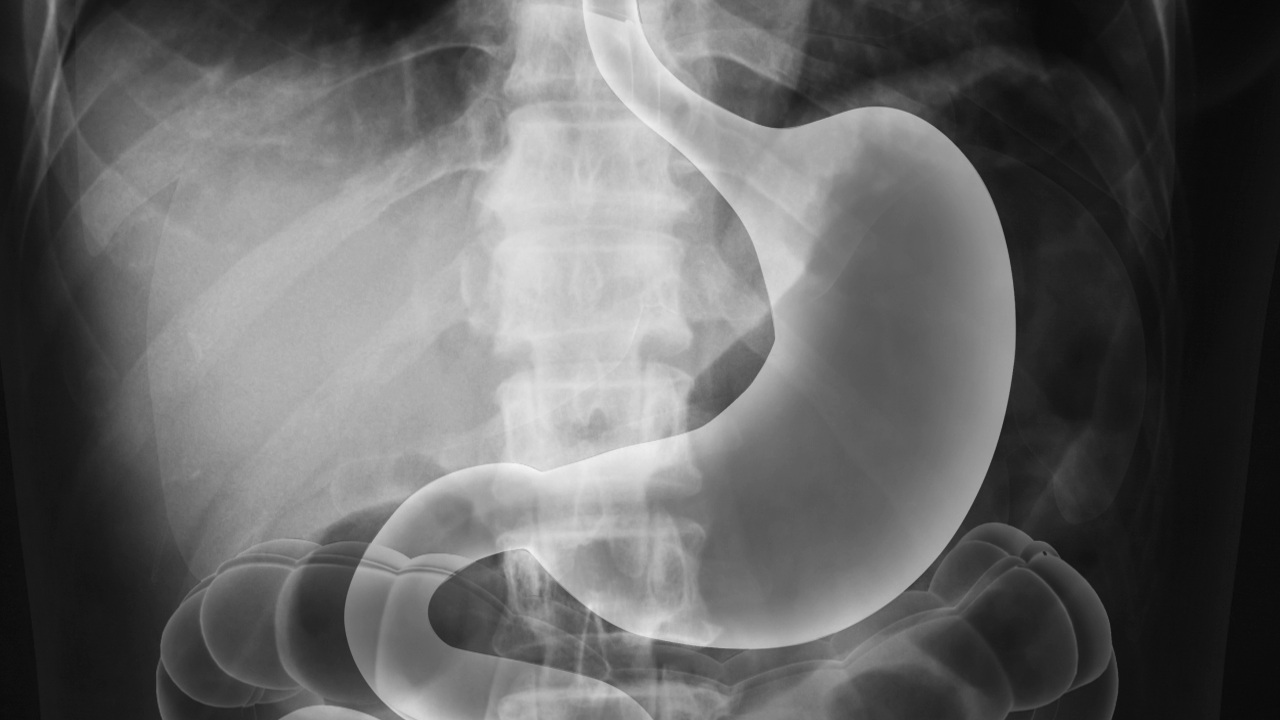

This is an x-ray exam. It can help your doctor identify problems with your esophagus, stomach, and the first part of your small intestine. You may benefit from this exam if you have a problem such as heartburn, indigestion or unexplained pain in your chest or abdomen.

Before the procedure, you change into a gown. You lie on an x-ray table. You need to swallow a special contrast liquid. Commonly, this liquid contains a metallic compound called barium sulfate. The contrast liquid coats the inside of your gastrointestinal tract. It helps make these structures visible.

The radiologist takes a series of x-rays. A special type of x-ray called a fluoroscope may also be used to record video. During the exam, you may be moved into different positions on the table. You may be asked to swallow a pill or a powder. You may be asked to drink a beverage through a straw. And, the radiologist may press on your abdomen. All of these things will help the radiologist capture images of your gastrointestinal tract.